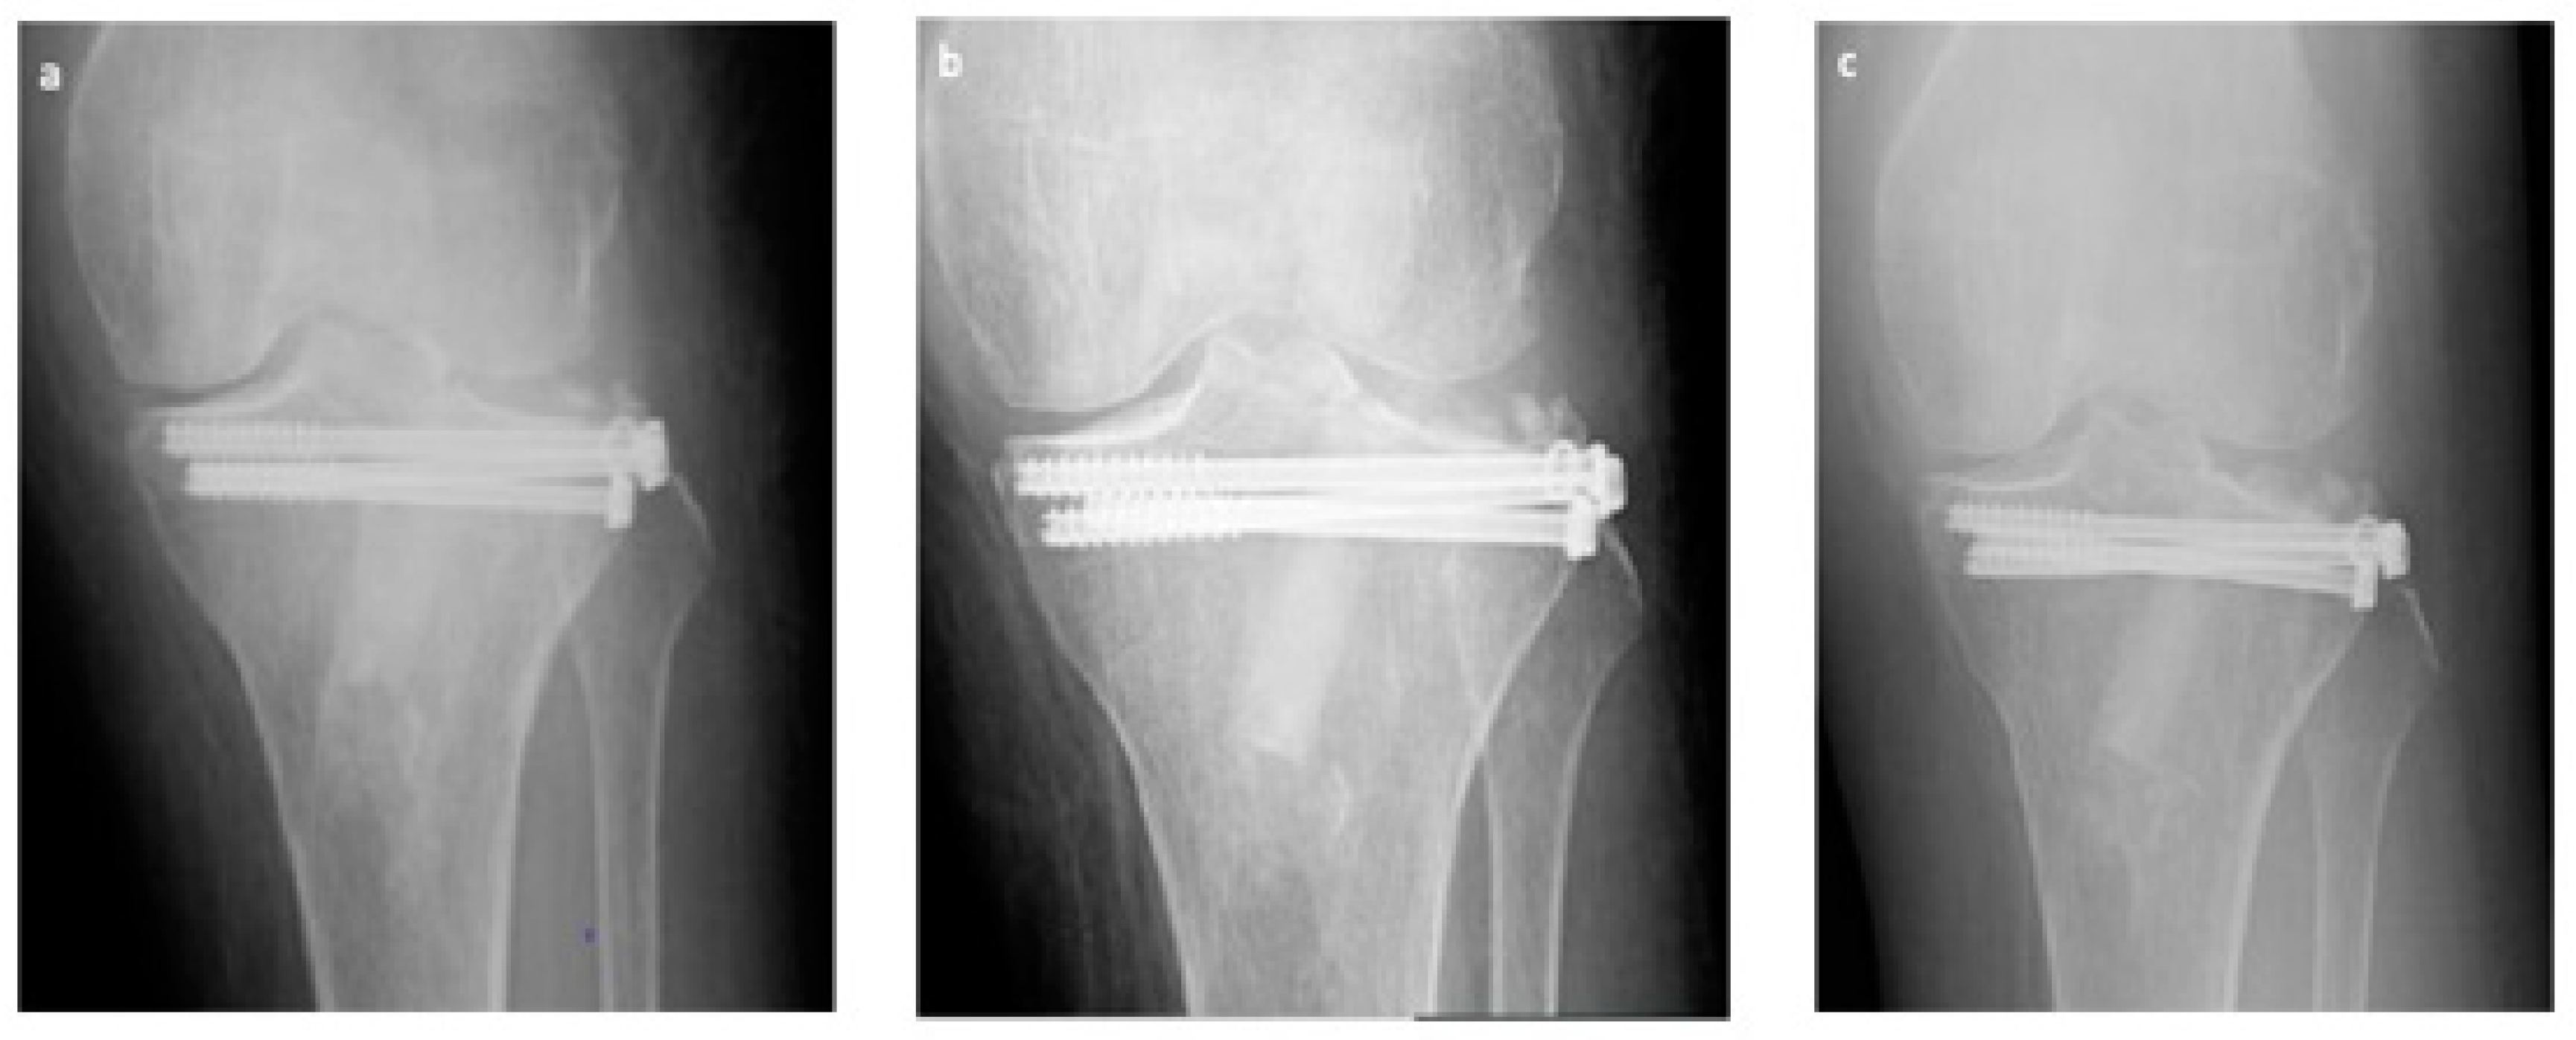

At each follow-up, we did not observe neither fracture recurrences nor radiographically noticeable subsidence or diastasis of the articular surface at follow up.

We did not detect pseudo-arthrosis, nor bone non-unions nor delayed consolidations [24]. Articular alignment was considered acceptable in all 34 cases at each evaluation (see also Figure 4).

At six months, X-rays images showed that all 34 fractures displayed a good consolidation rate, as confirmed by radiological reports. In particular, radiolucency of the xenografts was assessed [20], which became progressively more similar to that of the surrounding healthy bone tissue (see exemplificative Figure 1, Figure 2 and Figure 3 and comparative images in Figure 4).

Figure 4. Exemplificative case, in anteroposterior RX, at 1 (a), 3 (b), and 6 (c) months follow-up respectively, well evidencing good consolidation, absence of non-union or retarded consolidation and graft good integration confirmed by progressive loss of radiolucency of the graft itself.